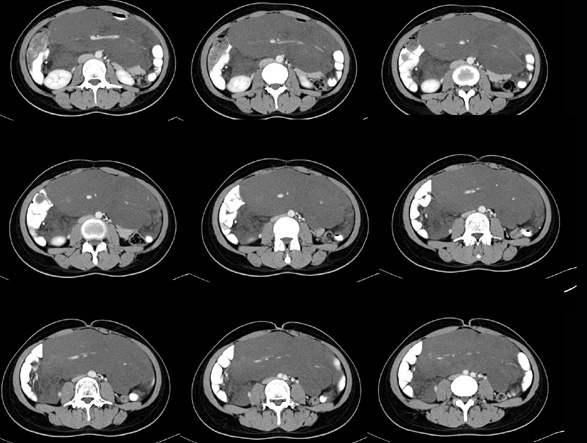

女性,28岁,停经3月,腹部膨隆1月,产前检查发现腹部占位

{肿块中心ct值27hu,增强后,动脉期、门脉期均无明显强化)

1 肠系膜肿块诸期无明显强化,肠系膜血管包绕其中但其周围仍见脂肪称“脂肪环征”;2 肠系膜血管远端较近端细,于重组像上见血管周围有强化结节为炎性结节,3肿块内见部分脂肪密度及少许点状钙化。4 腹膜后无肿大ln。

患者手术病理:腹腔囊性淋巴管瘤,象这样充满整个腹腔的的确很少见